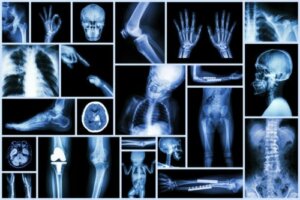

Som alle andre former for bildediagnostikk lar røntgenstråler oss lære om aspekter ved barnas kropper som vi ikke kan se med det blotte øye.

På legevakten hjelper et enkelt røntgenbilde oss med å bekrefte diagnosen brudd, oppdage tilstedeværelsen av et fremmedlegeme i luftveiene, eller finne ut om magesmerter krever kirurgisk behandling.

På andre medisinske områder og disipliner har røntgenbilder gitt uendelige fordeler, og det kan vi være sikre på. I tillegg er de raske, rimelige tester, tilgjengelig i de aller fleste helsesentre, og som generelt sett ikke krever sedasjon eller anestesi for å bli utført.